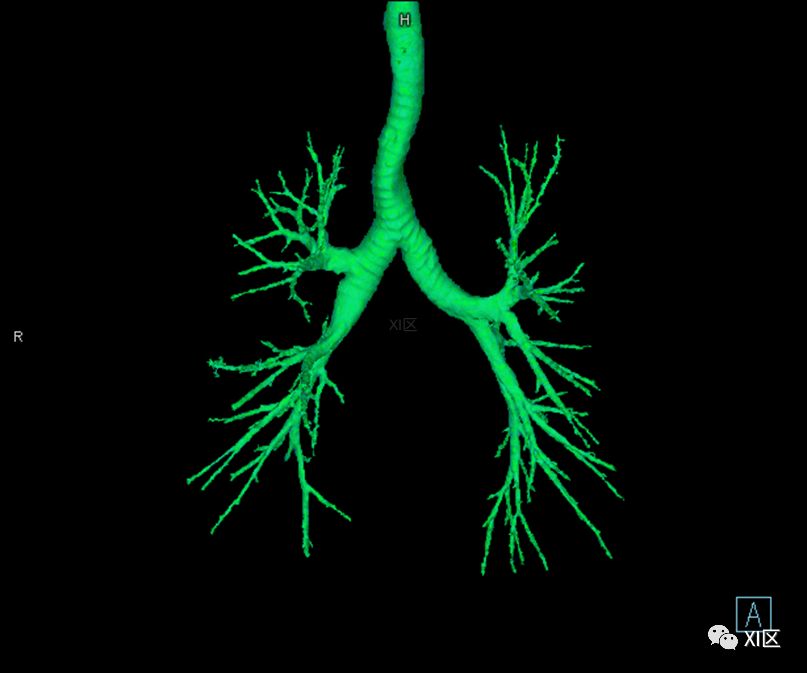

气管树的解剖

人的支气管(第1级)至肺泡约有24级分支。支气管经肺门入肺,分为叶支气管(第2级),右肺3支,左肺2支。叶支气管分为段支气管(第3~4级),左肺8支、右肺10支。段支气管就是肺的分段的依据。段支气管反复分支为小支气管(第5~10级),继而再分支为细支气管(第11~13级),细支气管又分支为终末细支气管(第14~16级)。从叶支气管至终末细支气管为肺内的导气部。终末细支气管以下的分支为肺的呼吸部,包括呼吸细支气管(第17~19级)、肺泡管(第20~22级)、肺泡囊(第23级)和肺泡(第24级)。

气管支气管形如树状,因此也称气管支气管树。

气管树